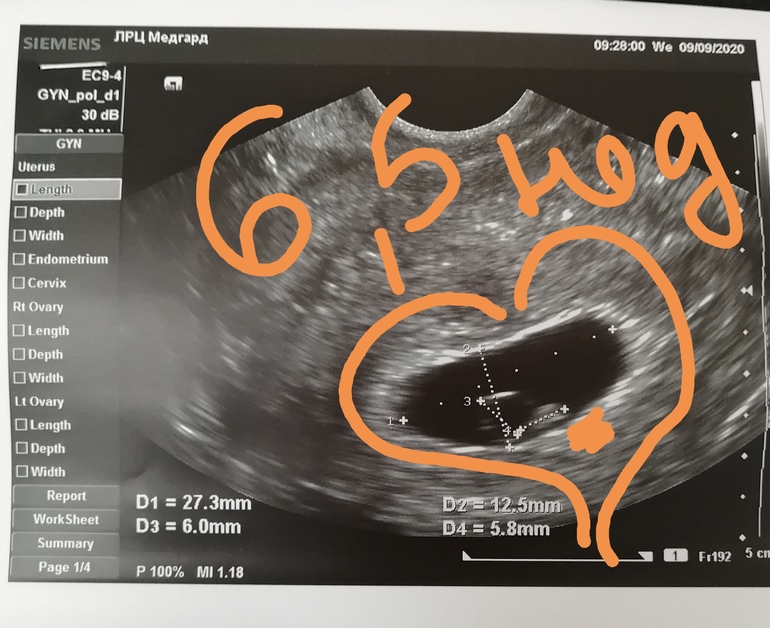

6.5 недель.

Поход к врачу. малышка подросла. Вернее её нашли. Ктр 6 мм. Пометила жёлтым маркером справа внизу и жм 6 мм. Сердечко стучит. Так миииило. Аж до слез. Сегодня сон вижу ночью. Прихожу на УЗИ. Врач говорит. Так. Срок 8 недель и я первый раз такое вижу, чтоб так рано писюн было видно. И поворачивает экран монитора, а там ножки, ручки и писюн. До сих пор смеюсь. Вот тебе и сон. Кто в рамзи разбирается?

Вот фото младшей в 6 недель и 4дня ПЯ 19 мм, КТР 6 мм, ЖМ 4 мм, ЧСС 123 уд/ мин